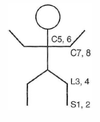

Spinal cord lesions: Poliomyelitis and Werdnig-Hoffmann disease What areas are affected? What are the Sx?

Lower motor neuron lesion only, due to destruction of anterior horns; flaccid paralysis

Lower motor neuron lesion only, due to destruction of anterior horns; flaccid paralysis What diseases (2) are associated with this?

Poliomyelitis and Werdnig-Hoffmann disease

Spinal cord lesions: ALS What areas are affected? What are the Sx?

Combined upper and lower motor neuron deficits with no sensory deficit; both upper and lower motor neuron signs.

Combined upper and lower motor neuron deficits with no sensory deficit; both upper and lower motor neuron signs. What disease is associated with this?

ALS

Spinal cord lesions: Complete occlusion of the anterior spinal artery What areas are affected? What are the Sx?

Spares dorsal columns and tract of Lissauer; upper throacic ASA territory is a watershed area, as artery of Adamkiewicz supplies ASA below ~T8

Spares dorsal columns and tract of Lissauer; upper throacic ASA territory is a watershed area, as artery of Adamkiewicz supplies ASA below ~T8 What disease is associated with this?

Complete occlusion of the anterior spinal artery

Spinal cord lesions: Tabes dorsalis (tertiary syphilis) What areas are affected? What are the Sx?

Degeneration of dorsal roots and dorsal columns; impaired proprioception, locomotor ataxia